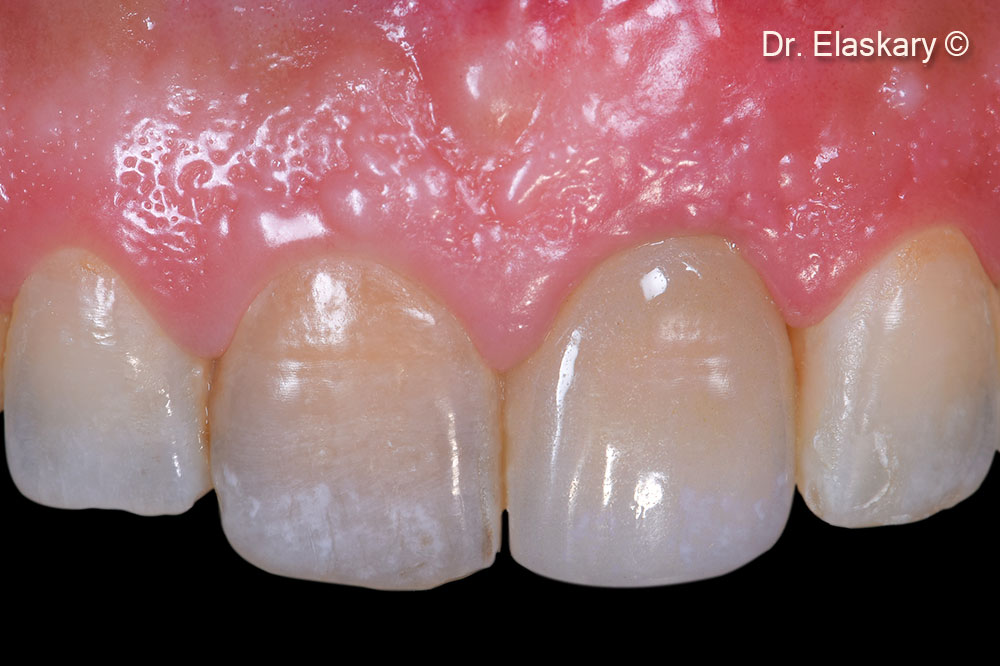

The final restoration in place shows a total restoration of the soft tissue margins